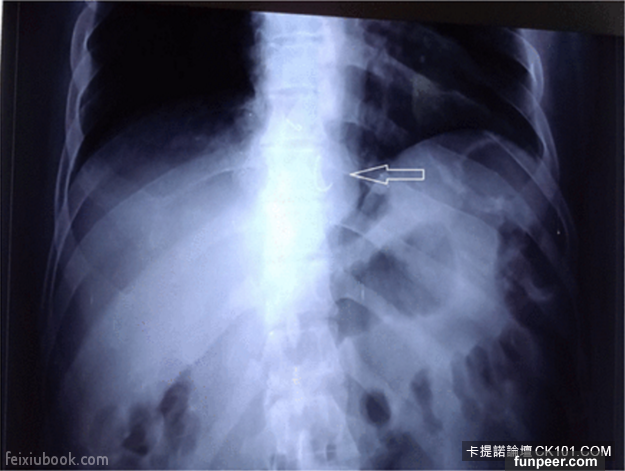

1.5公分長的針卡進一名4歲小男孩的腎臟裡。

這名男孩因為一直發燒又發冷,而且身體右側疼痛而到醫院,而且這樣的情形持續了3個月!從X光片中可以清楚看出他的右胸有尖刺狀的物體。最後外科醫生用腹腔鏡手術把針取出來,小男孩也沒事了。